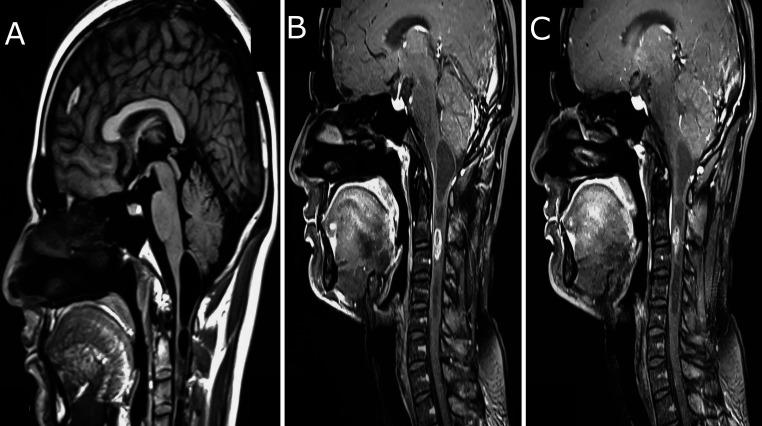

OBSERVATIONS

The authors reviewed the data of a young male with a 2-month history of neck pain and vertigo. Magnetic resonance imaging of the brain and cervical spine showed an intramedullary mass at C2-3 with a syrinx extending into the cervicomedullary junction. Laminectomy, myelotomy, and microsurgical excision of the mass under intraoperative neurological monitoring (IONM) were done. Postoperative pathology reported the specimen as a schwannoma.

观察结果

作者回顾了一名有2个月颈部疼痛和眩晕病史的年轻男性的数据。脑部和颈椎的磁共振成像显示C2-3水平有一个髓内肿块,伴有一个延伸至颈髓交界处的空洞。在术中神经监测(IONM)下进行了椎板切除术、脊髓切开术和肿块的显微手术切除。术后病理报告标本为神经鞘瘤。